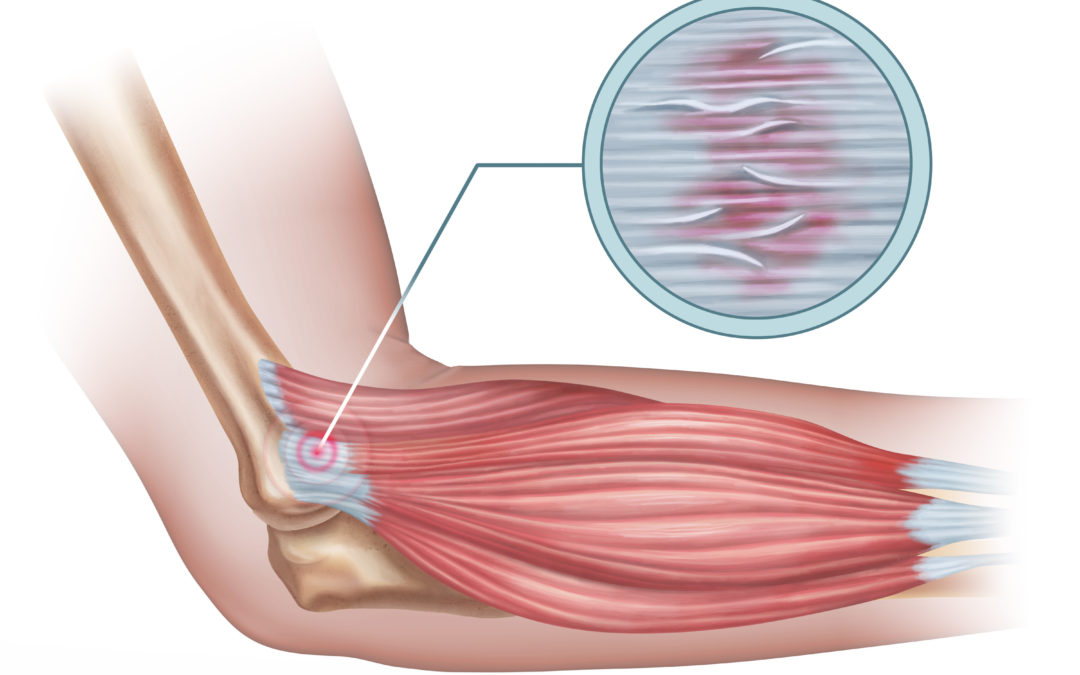

JUMPER’S KNEE (PATELLAR TENDONITIS). Peradangan Tendon Lutut

PENATALAKSANAAN CEDERA TENDINITIS PATELLA PADA ATLET BULUTANGKIS Zeth Boroh, Nani Cahyani Program Studi Ilmu Kedokteran Olahraga

Tendinitis Patella Adalah Penyebab Sakit Lutut » Klinik Patella

Cedera Tendinitis Patella Yang Sering Terjadi Pada Runner | ISMC | Indonesia Sports Medicine Centre

Tendinitis Patella

Pemeriksaan Klinis Tendinitis Patellaris (Jumper’s Knee)